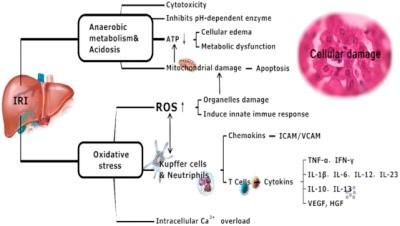

Review Article

J Liver Disease Transplant 2018, 7:1

10.4172/2325-9612.1000159